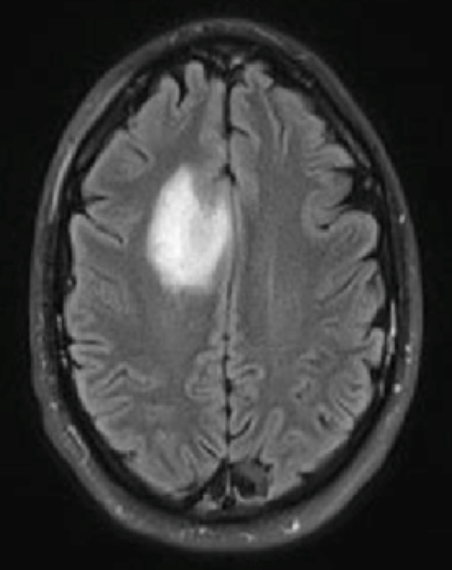

How to segment the tumor?

Binary segmentation mask

Segmentation

means dividing up an image into different structures